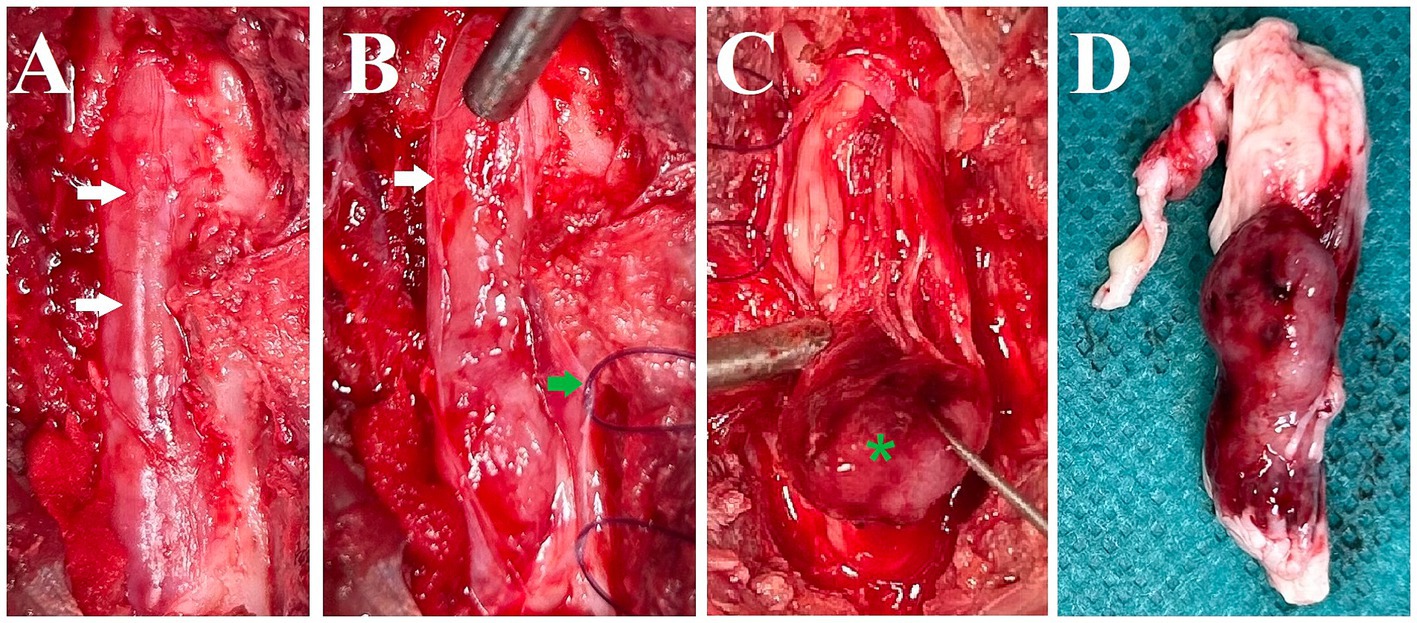

Treatment was initiated with prednisolone (0.6 mg/kg twice daily per os) but over the course of five days, the cat’s condition deteriorated to the extent that it could barely ambulate and exhibited urinary and fecal incontinence. Due to this swift deterioration, surgery was elected after discussion with the owner. A dorsal laminectomy was performed at L5-L6. The intradural and predominantly extraparenchymal red mass was visible through the dura mater (Figure 2A). After reflecting the dura mater (Figure 2B), using a surgical microscope, it was attempted to bluntly dissect the mass but it was found to be adherent to or fused with the spinal cord parenchyma and spinal nerve roots (Figure 2C). Following intraoperative consultation with the owner, including the options of further attempting to remove the tumor versus euthanasia as the owner had indicated the wish to be informed about possibly negative prognostic findings including difficulty removing the tumor, euthanasia was elected. The mass, along with the affected spinal cord segments and nerve roots, was extracted (Figure 2D), fixed in 10% buffered formalin, and submitted for histology.

Figure 2. Intraoperative pictures and a picture after removal of the spinal cord segments and nerve roots with the mass. (A) Dorsal aspect of the spinal canal after dorsal laminectomy. The dura mater is intact and the mass lesion is seen as red discoloration through it (white arrows). (B) Dura mater reflected (white arrow: edge of cut dura mater, green arrow: dura mater with stay suture). (C) Blunt dissection and caudal reflection of the main bulk of the mass lesion (green asterisk). It was attempted to bluntly dissect the mass but it was found to be adherent to or fused with the spinal cord parenchyma and spinal nerve roots. (D) Lateral (right) view of the removed spinal cord segments, nerve roots, and associated mass (directly post-mortem).